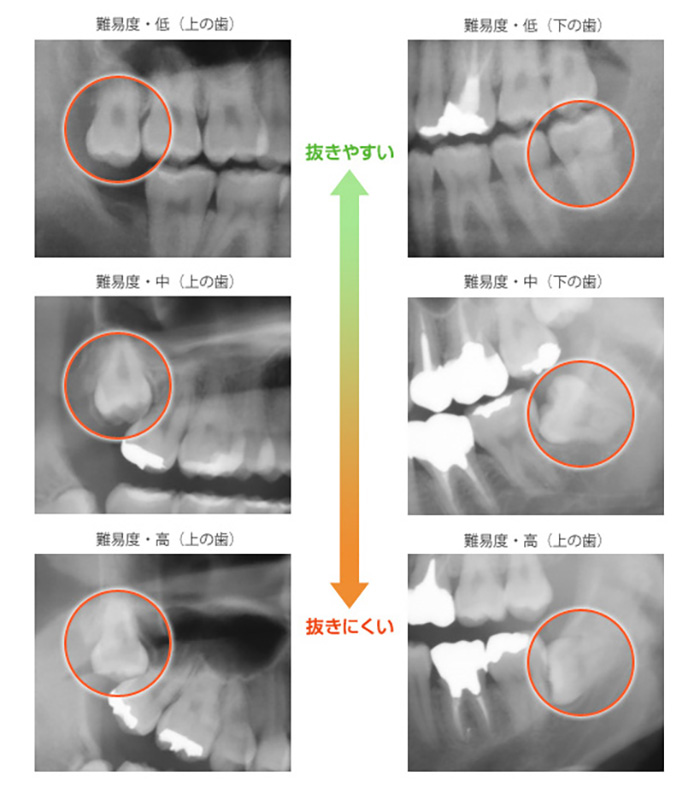

親知らず抜歯の難易度

親知らずの抜歯は、親知らずの生え方によって難易度が異なります。歯ぐきに埋まっている、斜めや横に生えている親知らずは、手術の難易度が高く負担が大きくなる傾向にあります。